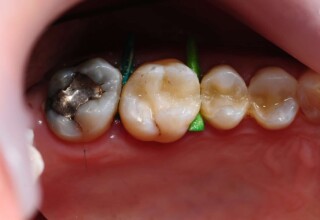

Posterior Tooth Root Canal Restoration with a Composite Resin Filling

The common restoration of a posterior tooth after a root canal is a crown. Its main purpose is to protect from fracture and concomitant extraction. In very few cases that specific criteria (mainly remaining tooth structure) are met or where finances predominate, an extensive composite filling can restore both aesthetics and function.

Restoration of a cracked molar with composite resin

Cracked teeth present a challenge in restorative dentistry both from the aspect of complexity of the restoration itself (usually large filings) and the necessary providings to avoid a complete fracture. The presented case demonstrates the simplest approach of a bonded direct restoration with composite resin. It is based on the principle of an adhesive filling that “holds” the remaining tooth structures “together”. The restored molar remained healthy for two years, then required a root canal and a crown was placed for maximum protection.